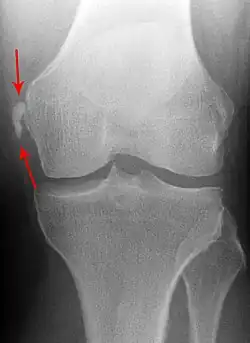

| Pellegrini-Stieda syndrome. Also visible is a fracture of the patella. |

Pellegrini–Stieda syndrome (also called Stieda disease and Köhler–Pellegrini–Stieda disease) is the ossification of the superior part of the medial collateral ligament of the knee. It is a common incidental finding on knee radiographs. It is named for the Italian surgeon A. Pellegrini (b. 1877) and the German surgeon A. Stieda (1869–1945).[1] While the eponym refers to Pellegrini and Stieda, the condition was first discovered by Köhler in 1903, before any namesakes. Pellegrini-Stieda combines the aforementioned radiographic findings and concomitant medial knee joint pain or restricted range of motion.[2]

Diagnosis is typically made on radiographs demonstrating the Pellegrini-Stieda syndrome sign accompanied by pain or restriction of range-of-motion of the knee joint.[2] Pellegrini-Stieda syndrome sign is typically described by a longitudinally linear opacity, which is a process that is describes characteristic of calcification in the soft tissue located medial to the medial femoral condyle.[2] This calcification seen on imaging represents the ossification of the medial collateral ligament, which typically does not develop until approximately three weeks after the initial injury.[2]It is important to note to distinguish this radiographic finding from that of a medial femoral condyle avulsion fracture, which is an injury in which a pulling force of a tendon or ligament fractures away a piece of the bone from its attachment site.[2]